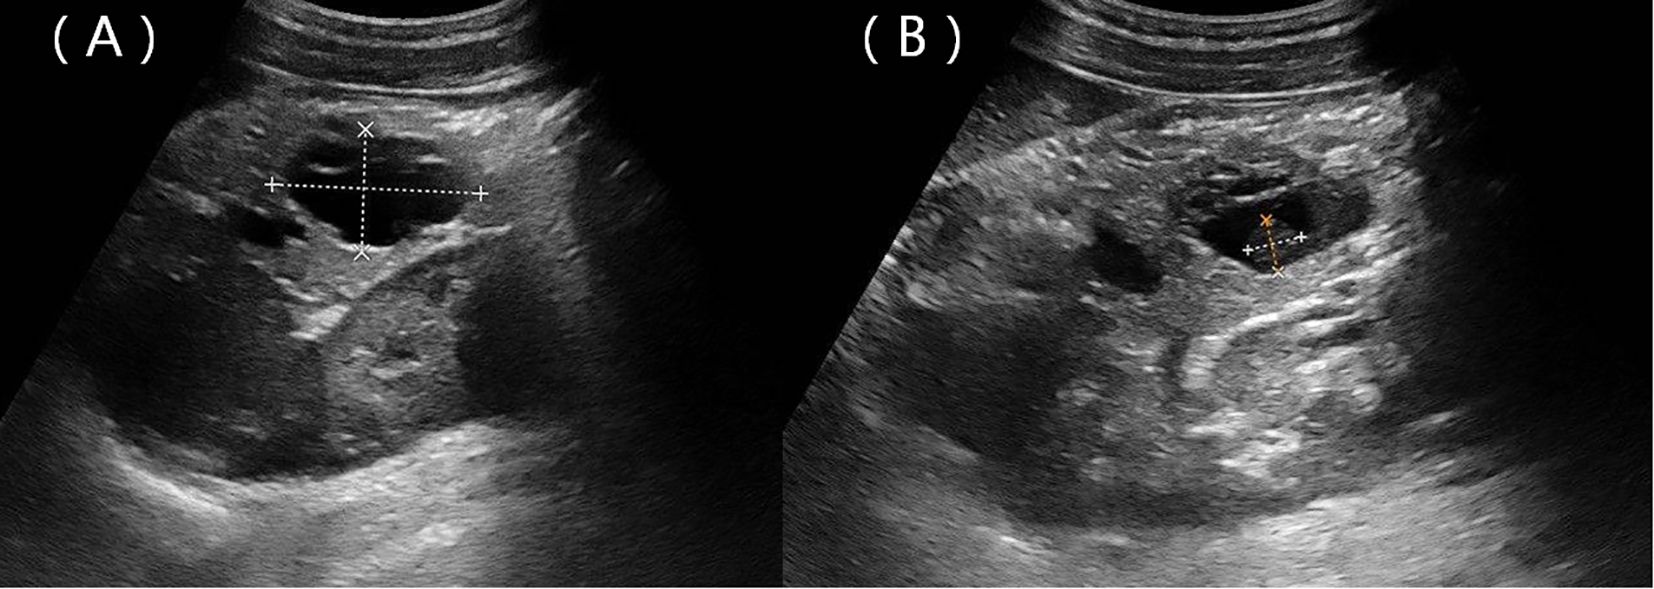

Figure 3

MRI and 3D imaging of the abdominal region in panels labeled A through F. Panels A, B, and C show axial MRI scans highlighting organs such as the liver and kidneys. Panel D presents a coronal MRI emphasizing vascular structures. Panel E shows a 3D reconstruction of abdominal vessels and organs. Panel F, highlighted by a red box, provides a close-up of the 3D model, detailing blood vessels and organs in red, blue, green, and yellow.

Figure 3. Contrast-enhanced MRI scans. The solid components and septa were slightly enhanced in the arterial phase, with delayed enhancement observed in the venous and delayed phases (A–C). The coronal MIP image displays enlargement of the portal vein and tortuous dilation of blood vessels in the splenic hilum (D). (E) Preoperative three-dimensional MRI of the tumor and adjacent structures. (F) Cystic (light blue) and solid (yellow) components of the tumor.

A 22-year-old woman was admitted to the hospital in August 2022 after a routine medical checkup revealed a cystic-solid mass in her pancreas. The patient’s past medical history, personal history, and family history were unremarkable. Physical examination of the abdomen revealed no notable findings. An ultrasound revealed a cystic mass in the tail of the pancreas with clear margins, multiple hyperechoic septa, and isoechoic nodules at the edge (Figure 1). Furthermore, a computed tomography (CT) plain scan revealed a cystic-solid mass in the body and tail of the pancreas, which appeared regularly shaped with solid components of equal density and septa (Figure 2A), measuring approximately 3.6 × 2.5 cm. There was no clear demarcation of the lesion from the adjacent organs and the peritoneum. To further assess the nature of the lesion, the patient underwent magnetic resonance imaging (MRI). The MRI findings revealed a cystic-solid mass in the body and tail of the pancreas with septa. The solid components and septations appeared isointense on the T1-weighted image (T1WI), while they were slightly hyperintense on the T2-weighted image (T2WI). The cystic components were hypointense on T1WI and hyperintense on T2WI (Figures 2B, C). The lesion was found to adhere tightly to the adjacent organs and the peritoneum. On diffusion-weighted imaging (DWI), the solid components displayed hyperintensity (b = 800 s/mm2) and hypointensity on the apparent diffusion coefficient (ADC) map (Figures 2D, E). Gadolinium-enhanced scanning revealed a slight enhancement of the solid components and septa in the arterial phase (Figure 3A), followed by continuous enhancement in the venous and delayed phases (Figures 3B, C). However, the cystic component did not display enhancement. The maximum intensity projection (MIP) image indicated an enlargement of the portal vein and tortuous dilation of blood vessels in the splenic hilum (Figure 3D). Moreover, Figures 3E, F display the preoperative three-dimensional MRI of the tumor and adjacent structures. The preoperative diagnosis was a solid pseudopapillary tumor of the pancreas.

The operative record documented an indistinct demarcation between the lesion and neighboring organs and peritoneum, indicating the invasiveness of the lesion. An enlarged portal vein and the tortuous dilation of blood vessels in the splenic hilum, observed in the MIP image, were also confirmed during surgery. The splenic vein was wrapped by the tumor, leading to these alterations. Despite its aggressive behavior, the tumor is usually benign in nature and can be cured via surgical resection. Therefore, clinicians should exercise caution to avoid misdiagnosis and unnecessary overtreatment.